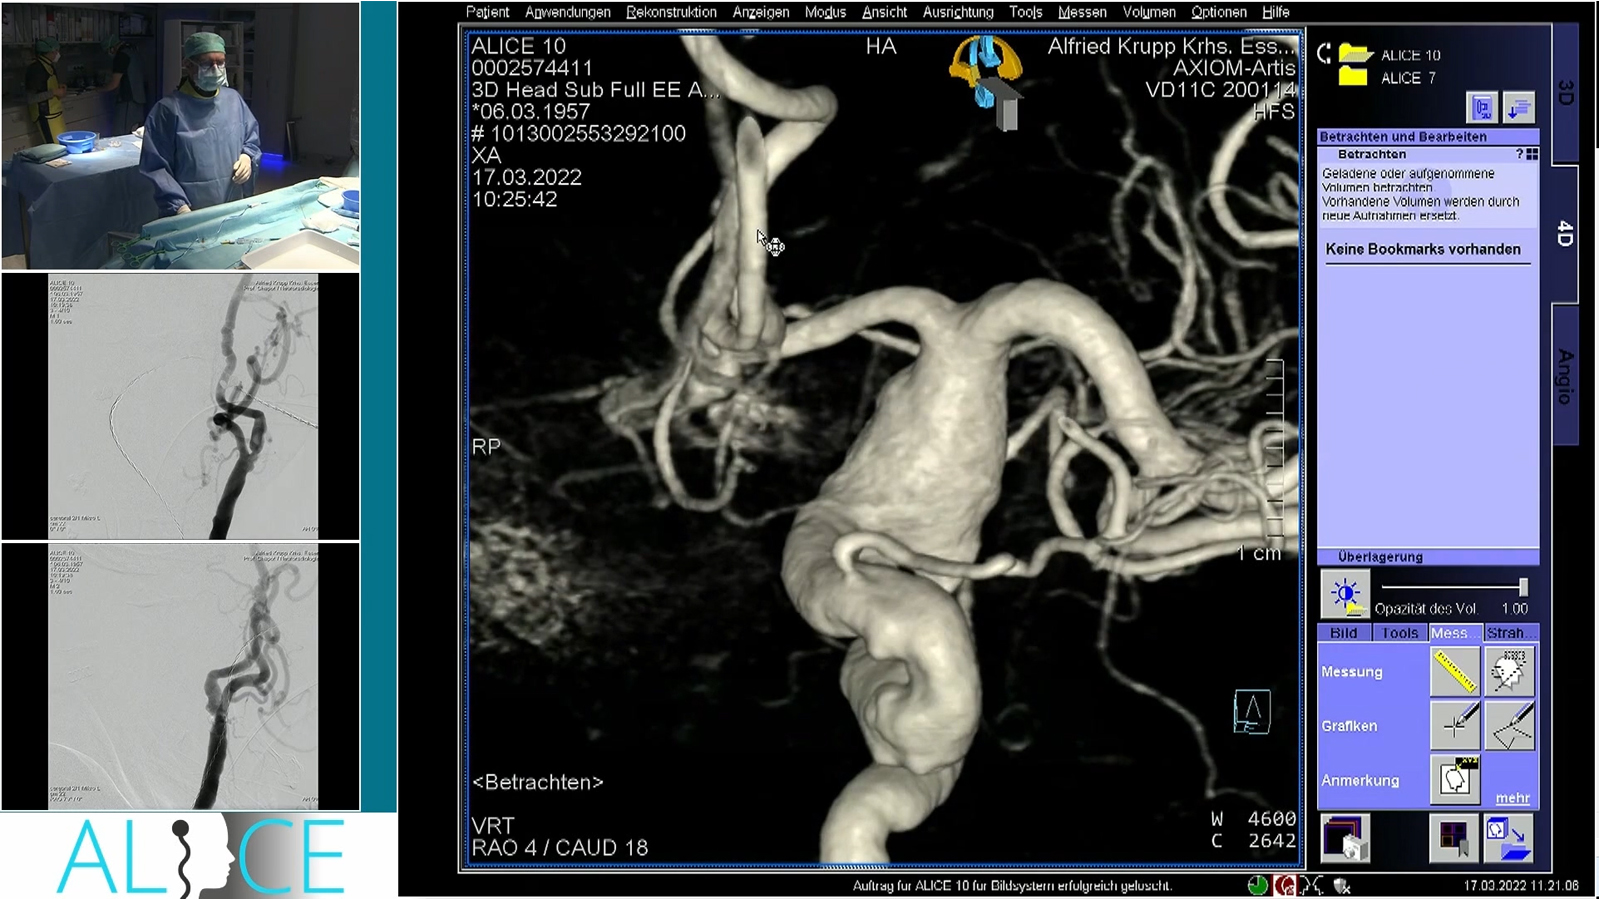

Giant fusiform basilar aneurysm treated by Stenting with Rex and occlusion of V4 on one side